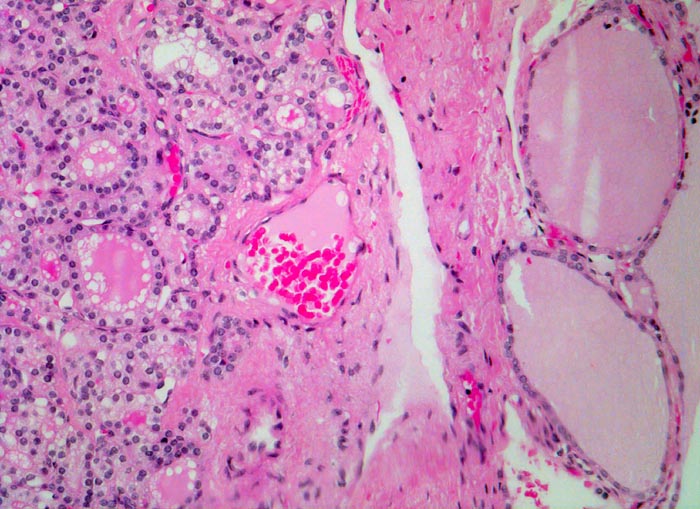

• Zeichen gesteigerter hormoneller Aktivität im Adenom:

• Kleine Drüsenlumina.

• Teils mehrreihiges kubisches bis zylindrisches Epithel.

• Fehlendes oder nur spärliches helles Kolloid mit zahlreichen Resorptionsvakuolen.